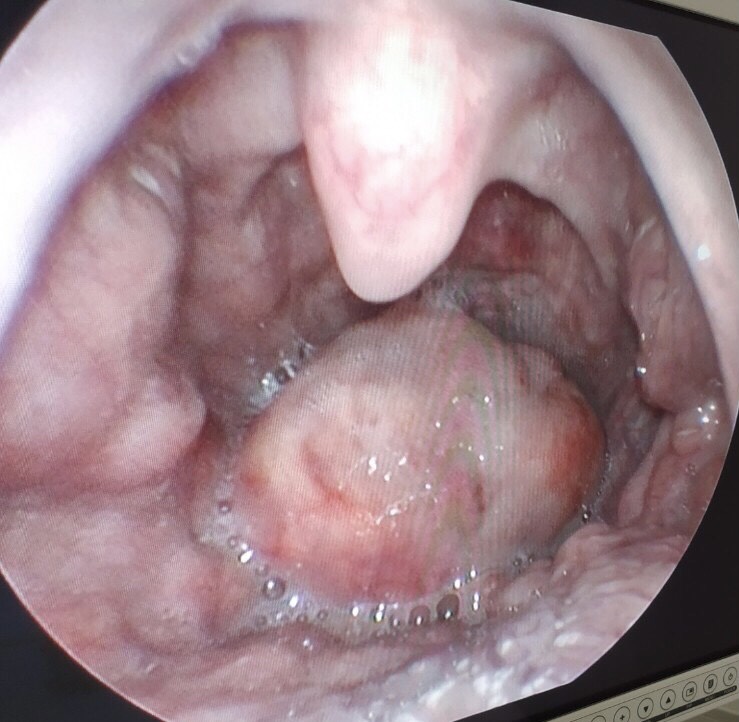

viem nap thanh nhiet Hình ảnh trước khi phẫu thuật

Với tình trạng sức khỏe của bệnh nhân khi tới thăm khám, bác sĩ đã tiến hành tiêm kháng sinh và thuốc chống phù nề liều cao. Tuy nhiên, sau khoảng chưa đầy 1 tiếng theo dõi thì tình trạng của bệnh nhân không giảm, cảm giác ngứa họng tăng lên, khó thở, SPO2 máu giảm xuống còn 90 - 91%.  Lúc này nắp thanh thiệt của bệnh nhân phình to nhanh, gấp 3 lần lúc mới vào viện.